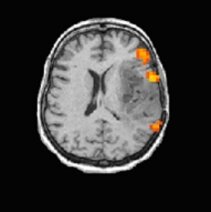

Die funktionelle Magnetresonanztomographie (fMRT) ist auch unter ihrer englischen Bezeichnung functional magnetic resonance imaging (fMRI) bekannt. Es ist eine Weiterentwicklung der Magnetresonanztomographie (MRT), mit deren Hilfe Stoffwechselvorgänge im Gehirn erkannt werden können. Das Verfahren ist ebenfalls nicht-invasiv und schmerzlos. Die Bilder, die durch eine Untersuchung mit dem fMRT gewonnen werden, werden sowohl zur Diagnostik als auch zur Vorbereitung und während der Durchführung eines neurochirurgischen Eingriffs verwendet